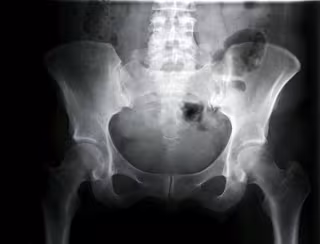

El número de fracturas de caderas en las mujeres entre 65 y 80 años ha disminuido de media un 0,2 por ciento, mientras que en los hombres ha aumentado un 0,4 por ciento, según un estudio del Instituto de Investigación en Atención Primaria Jordi Gol (IDIAP Jordi Gol).

Para determinar estos resultados de este estudio, publicado en el artículo 'Changing trends in the epidemiology of hip fracture in Spain' y consultado por Europa Press, los investigadores analizaron la cantidad de fracturas de cadera en dos periodos distintos de tres años separados por diez años ambos (1997-2000 y 2007-2010).

En realidad, y pese la disminución de fracturas de cadera en las mujeres, hubo un mayor número de casos en este colectivo (415.421, por 119.857 en los hombres). Aún así, comparando ambos periodos, en la segunda parte del estudio hubo menos casos de fracturas en las mujeres que en el primero, mientras que en los varones incrementó este número en el segunda parte en comparación con el primera.

Así lo confirma el investigador del IDIAP y coordinador del proyecto, el doctor Rafael Azagra. "El análisis de los resultados muestra que la tasa de incidencia en las mujeres, en los últimos años, aunque sigue creciendo lo hace a un ritmo menor, es decir, se observa una desaceleración, mientras que en los hombres se mantiene un aumento constante", ha indicado.